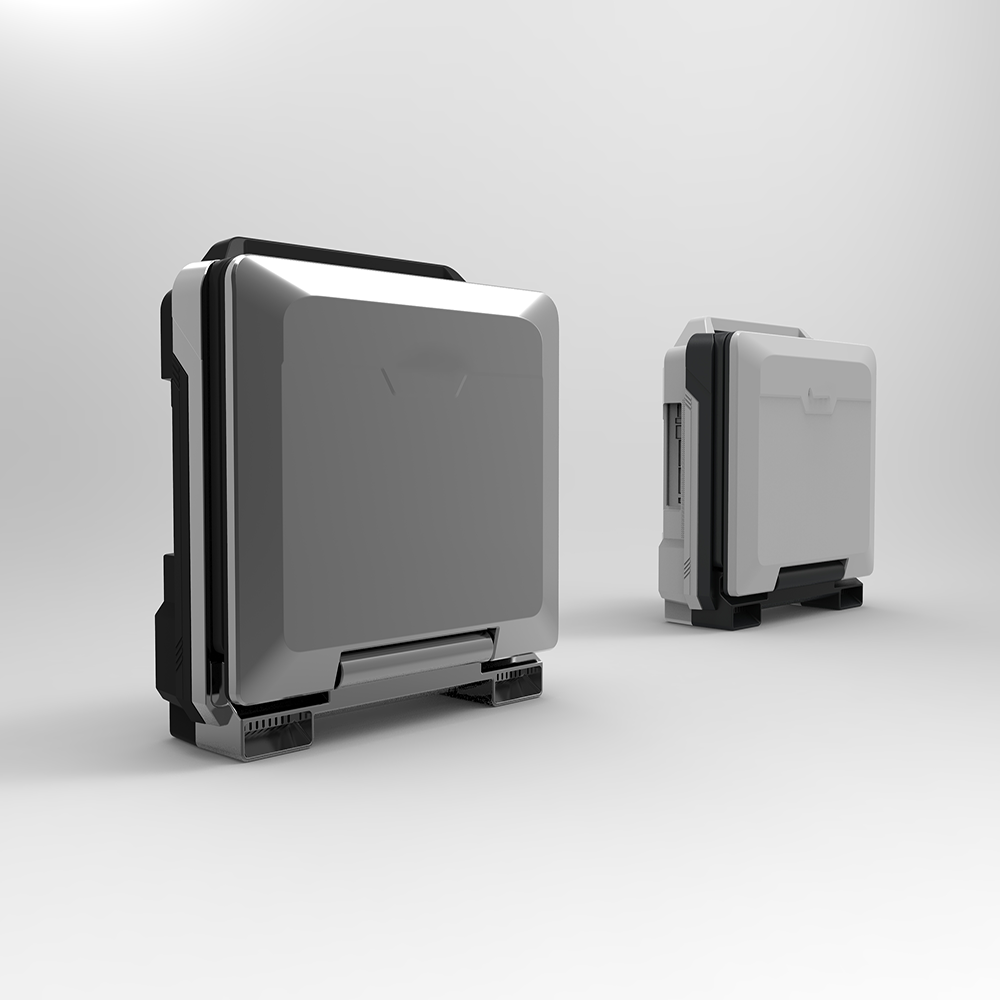

Amain AMDV-900 ultrasound manufacturers portable B/W ultrasound machine handheld veterinary ultrasound scanner

Product name | Amain laptop/portable B/W ultrasound machine |

Amain AMDV-900 black and white portable ultrasound system as a high-array, high-definition, multi-function all-digital true 96 yuan laptop ultrasound diagnostic instrument has:

main futures of portable medical pet use ultrasound scanner for obstetrics 1. High-precision full-digital imaging technology, progressive scanning without flickering, delicate and clear images2. 12 inch LED high definition monitor. Only 6.5kg Easy for taking, portable, lighter3. Professional embedded ultrasonic platform4. high density probe, broadband and frequency conversion technology, increase the image quality greatly5. Backlight silica gel keyboard, Photoelectricity track control6. Intellectualized TGC gain control of the whole paragraph8, precisely adjustment image density7. Wide applications: Abdominal, OB/GYN, Urology, Cardiology, Small parts examination etc.8. USB port: storable and readable